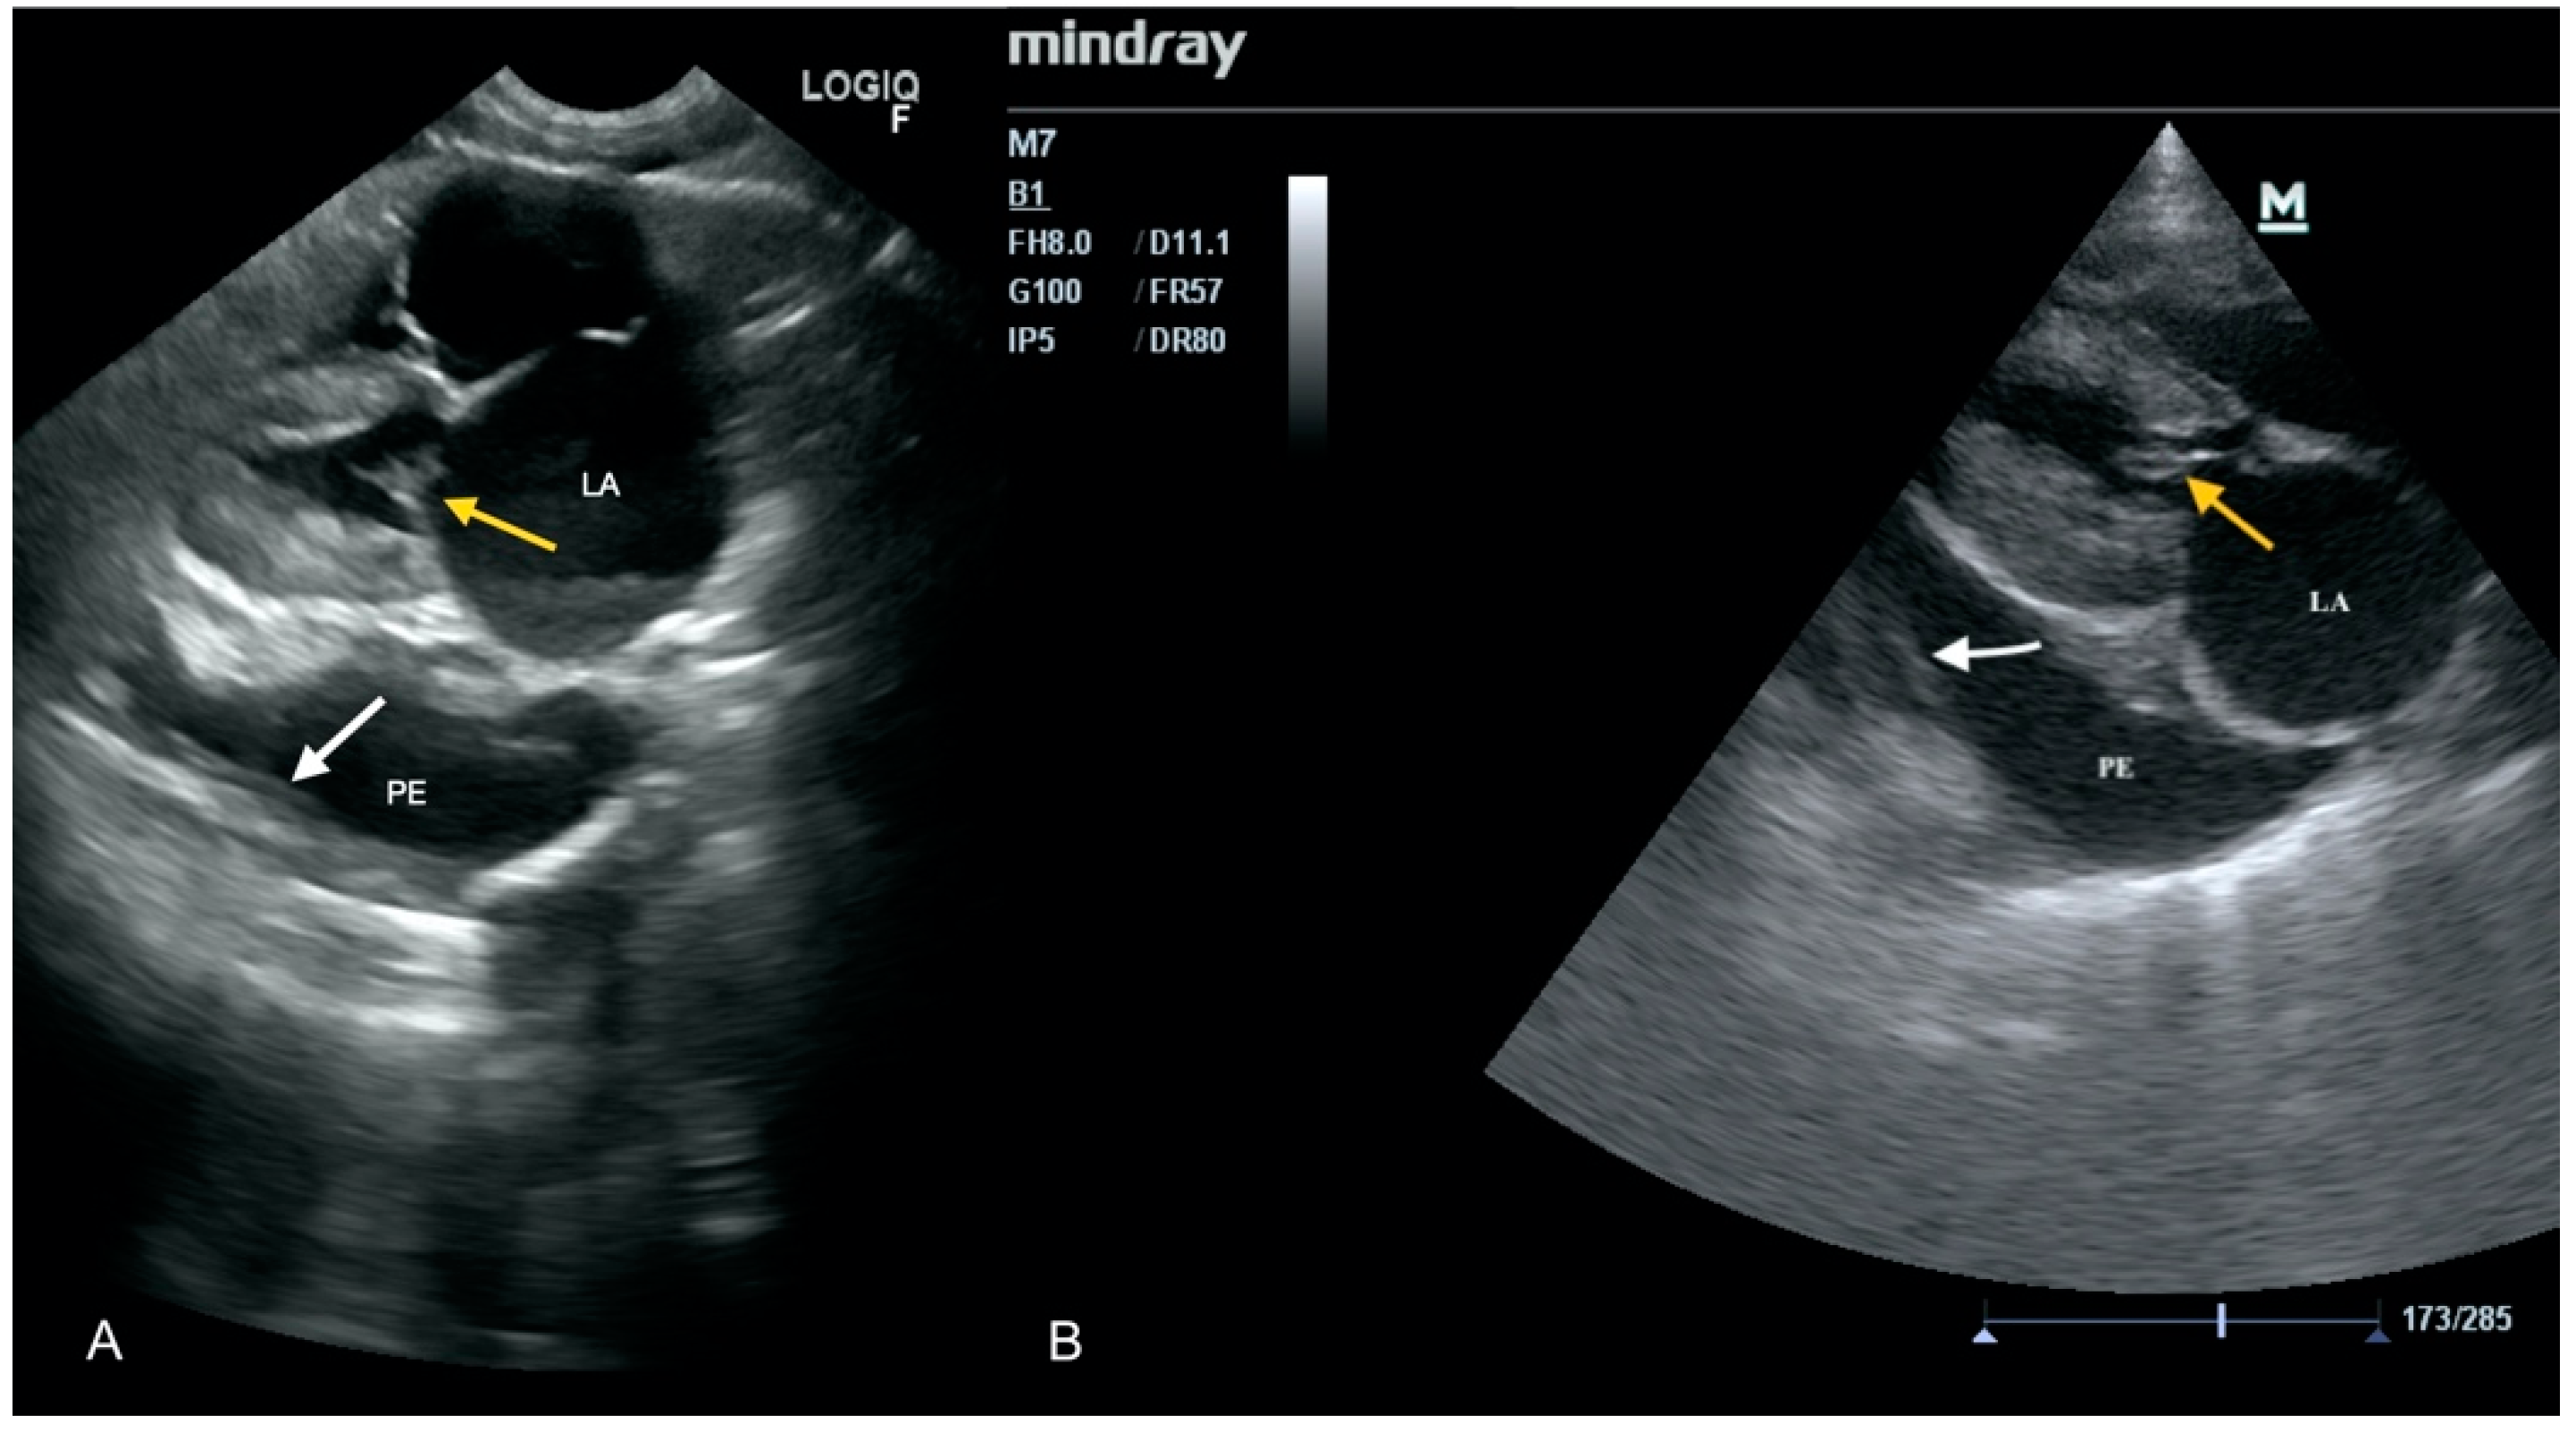

3.1. Case No. 1